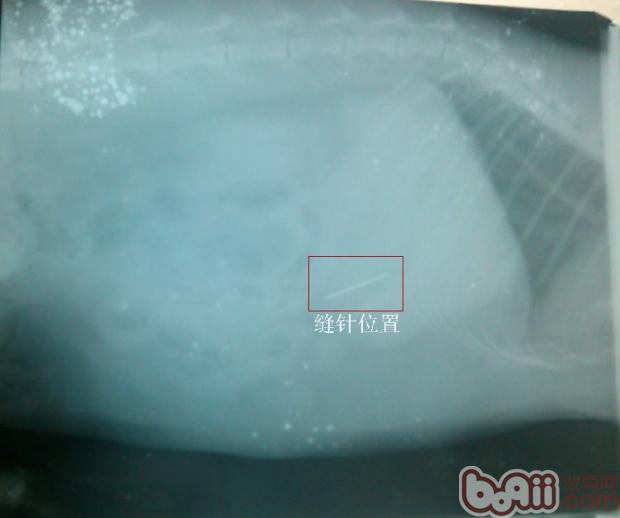

2、診斷:X光片檢查可見胃底部出現針狀物,根據發病情況、臨床檢查及X線照片,確診為胃內異物。且胃內異物是尖銳的針,為了防止胃出血和胃穿孔,貓胃內異物的治療及體會遂施行胃切開術。